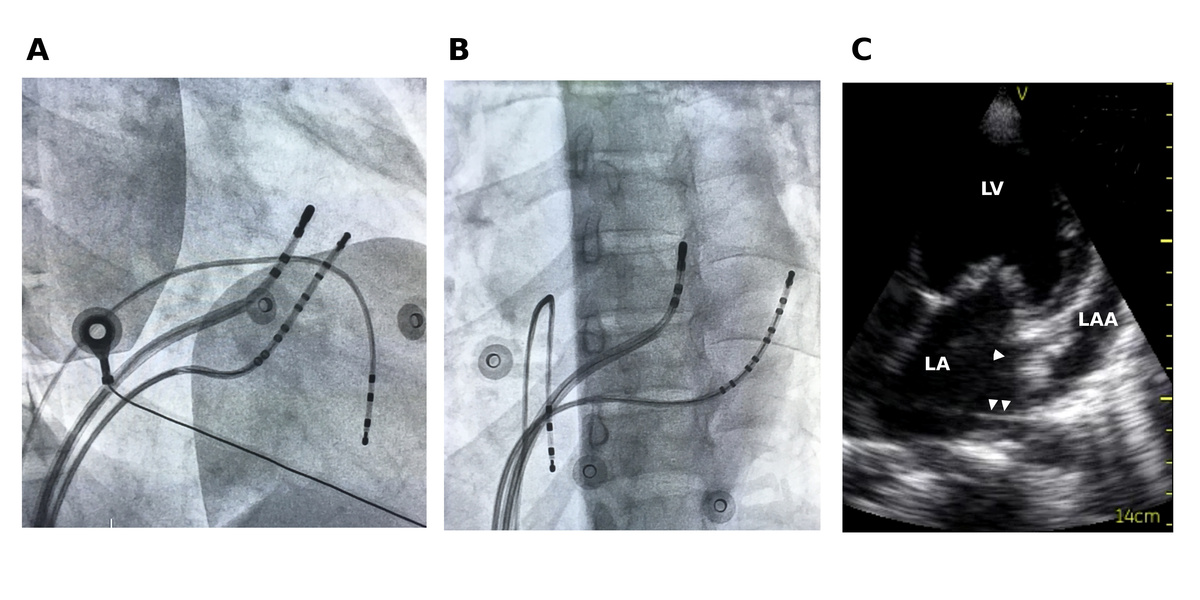

Non annular location of AP

fig2.jpg

fig3.jpg